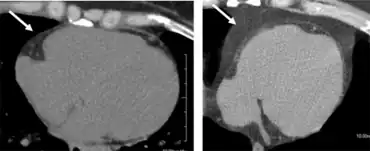

The key sign of metabolic syndrome is central obesity, also known as visceral, male-pattern or apple-shaped adiposity. It is characterized by adipose tissue accumulation predominantly around the waist and trunk.[4] Other signs of metabolic syndrome include high blood pressure, decreased fasting serum HDL cholesterol, elevated fasting serum triglyceride level, impaired fasting glucose, insulin resistance, or prediabetes. Associated conditions include hyperuricemia; fatty liver (especially in concurrent obesity) progressing to nonalcoholic fatty liver disease; polycystic ovarian syndrome in women and erectile dysfunction in men; and acanthosis nigricans.

Research shows that Western diet habits are a factor in development of metabolic syndrome, with high consumption of food that is not biochemically suited to humans.[23] Weight gain is associated with metabolic syndrome. Rather than total adiposity, the core clinical component of the syndrome is visceral and/or ectopic fat (i.e., fat in organs not designed for fat storage) whereas the principal metabolic abnormality is insulin resistance.[24] The continuous provision of energy via dietary carbohydrate, lipid, and protein fuels, unmatched by physical activity/energy demand, creates a backlog of the products of mitochondrial oxidation, a process associated with progressive mitochondrial dysfunction and insulin resistance.

Central obesity is a key feature of the syndrome, being both a sign and a cause, in that the increasing adiposity often reflected in high waist circumference may both result from and contribute to insulin resistance. However, despite the importance of obesity, affected people who are of normal weight may also be insulin-resistant and have the syndrome.[29]

It is common for there to be a development of visceral fat, after which the adipocytes (fat cells) of the visceral fat increase plasma levels of TNF-α and alter levels of other substances (e.g., adiponectin, resistin, and PAI-1). TNF-α has been shown to cause the production of inflammatory cytokines and also possibly trigger cell signaling by interaction with a TNF-α receptor that may lead to insulin resistance.[35] An experiment with rats fed a diet with 33% sucrose has been proposed as a model for the development of metabolic syndrome. The sucrose first elevated blood levels of triglycerides, which induced visceral fat and ultimately resulted in insulin resistance. The progression from visceral fat to increased TNF-α to insulin resistance has some parallels to human development of metabolic syndrome. The increase in adipose tissue also increases the number of immune cells, which play a role in inflammation. Chronic inflammation contributes to an increased risk of hypertension, atherosclerosis and diabetes.[36]